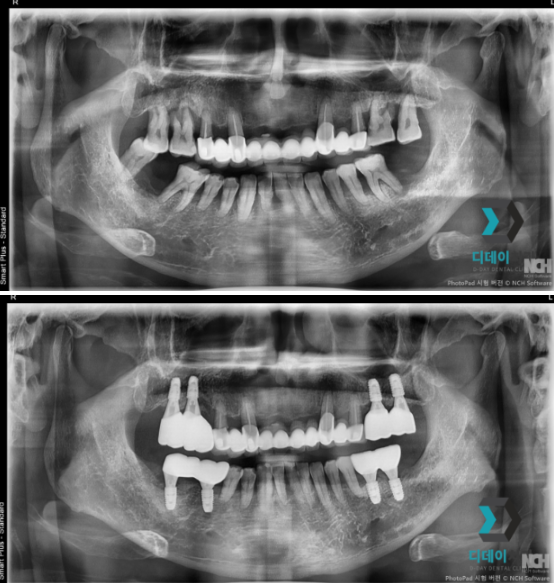

양쪽 위아래 어금니 치주염으로 내원하신 환자분입니다.

양쪽 어금니 심한 치주염으로 인해 발치 후

즉시 임플란트 식립 진행했습니다

양쪽 위아래 어금니 치주염으로 발치 후 즉시 임플란트 식립

25-07-15